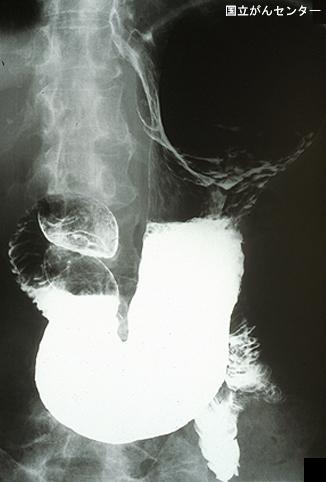

症例提示(所在地,施設名等): 東京都・ 国立がんセンター中央病院と九州がんセンターの共同作成

TIC症例

症例登録日 2003/10/14

画像数 32

性別 女性

年齢 65-69

取得年代 1990-1994

画像ID:5982

[ 画像ID:5982 ]

■詳細データ

疾患(病理主体)の分類悪性上皮性腫瘍/腺癌

部位(臓器別)食道/下

検査方法X-P